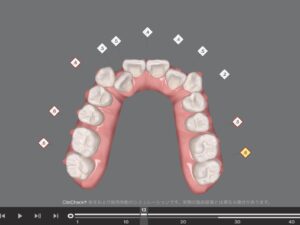

クリンチェックではこのように、どこをどれくらい、何枚目のアライナーの時に削るのかが表示されます。

私は上下合わせて22箇所IPRをする予定です。